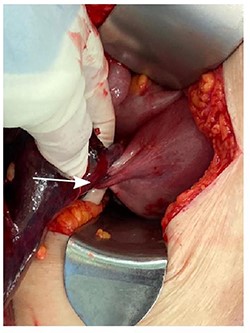

An urgent CT abdomen and pelvis (CTAP) revealed a change in orientation of the large cystic adnexal mass with possible signs of intra-tumoural haemorrhage (Fig. 1). Blood investigations found a haemoglobin level of 9.6 g/dL from a baseline of 12.6 g/dL, leukocytosis of 15.5 × 109/L and lactate was slightly elevated at 1.5 mmol/L.

CT abdomen and pelvis (CTAP) showing acute change in orientation of the right ovarian mass before (A) and after (B) colonoscopy.

A diagnosis of right ovarian torsion was made and the patient underwent exploratory laparotomy, right salpingo-oophorectomy with intra-operative frozen section and omentectomy. Intra-operatively, torsion of right gonadal vessels was noted (Fig. 2). The right gonadal vessels were taken between ties. The right fallopian tube was ligated. Frozen section from the right salpingo-oophorectomy showed features of benign serous cystadenoma with extensive haemorrhagic infarction in keeping with torsion. There was no evidence of malignant cells. Omentectomy was performed and sent for frozen section, which returned with no evidence of malignancy. The abdominal cavity was washed thoroughly and closed with sutures.